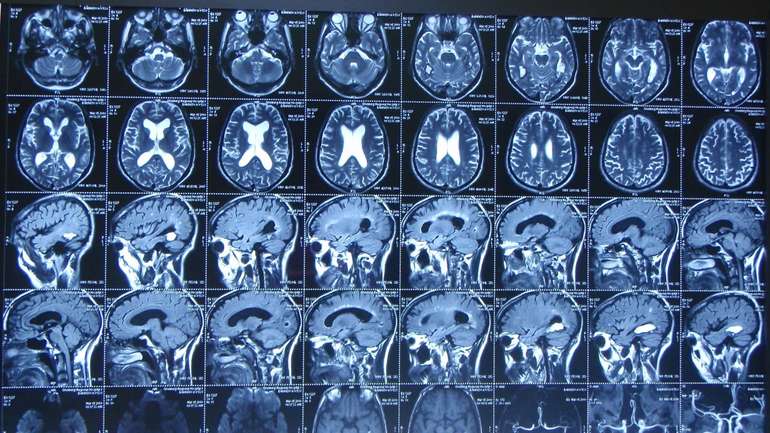

Накопиченням жиру в мозку провокує хворобу Альцгеймера

Фото: Nature

Американські науковці знайшли нову причину невиліковного захворювання. З'ясувалося, що проблема у збільшенні крапель жиру у клітинах мозку.